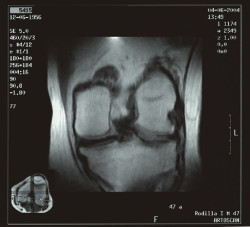

El reemplazo total de rodilla es rentable para pacientes con artrosis y pacientes con obesidad

La cirugía de reemplazo total de rodilla es rentable en pacientes con obesidad severa (IMC de 40 kg / m2 o más) y artrosis en etapa terminal. Por lo general, los cirujanos dudan en realizar esta intervención en estos pacientes porque tienden a tener altas tasas de complicaciones después de la cirugía, según un análisis de rentabilidad publicado en `Annals of Internal Medicine`.